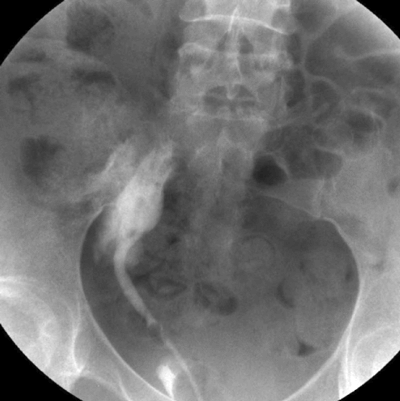

You have been called into the gynaecology operating theatre. They are performing a laparoscopic hysterectomy and suspect the right ureter has been injured.

1. Retrograde ureteropyelogram. Contrast extravasation, demonstrating an iatrogenic injury to the right lower ureter.

2. AAST ureteric injury severity scale.

Grade 1

Type of injury Haematoma

Description of injury Contusion or haematoma without devascularisation

Grade 2

Type of injury Laceration

Description of injury <50% transection

Grade 3

Description of injury ≥50% transection

Grade 4

Description of injury Complete transection with <2cm devascularisation

Grade 5

Description of injury Avulsion with >2cm of devascularisation

3. Surgical principles are: debride necrotic tissue, spatulate ureteral ends, water-tight mucosa-to-mucosa anastomosis with absorbable sutures, internal stenting and external draining. Grade 1 - Conservative +/- ureteric stent. Grade 2/3 - Ureteric stent +/- primary closure with suture. Grade 4/5 - Ureteric reconstruction.